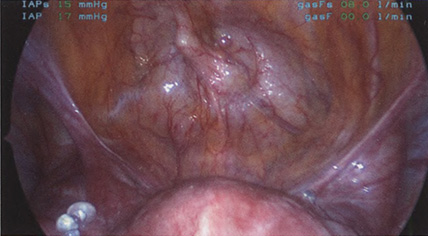

Если оставить в стороне эти достоинства и недостатки, то техника лапароскопической гистерэктомии фактически идентична технике лапаротомической гистерэктомии. В самом начале операции, если она выполняется лапароскопическим методом, необходимо осмотреть всё операционное поле, воспользовавшись для этого панорамным обзором (рис. 12-33—12-37). Операцию начинают с коагуляции и пересечения круглых связок, чем обеспечивается доступ к широкой связке (рис. 12-38—12-40). Брюшину, переходящую с купола мочевого пузыря на переднюю поверхность матки, вскрывают. Пузырь отсепаровывают от матки острым путём (рис. 12-41). После этого вскрывают задний листок широкой связки, а затем принимают решение, оставлять или удалять яичники. Если принято решение оставить яичники, то коагулируют и пересекают собственные связки яичников и маточные трубы (рис. 12-42). Если принято решение удалить яичники (то есть выполнить сальпингоофорэктомию), то с обеих сторон выполняют диссекцию мочеточников от воронко-тазовых связок, которые затем отсепаровывают, коагулируют и пересекают (рис. 12-43). Затем ткань широкой связки отделяют от маточных сосудов (отпрепаровывая их), изолировав, таким образом, мочеточники от маточных сосудов (рис. 12-44 А). Восходящие ветви маточных сосудов коагулируют справа и слева, а затем пересекают (рис. 12-44 Б, В).

Рис. 12-37. Левая круглая связка натянута, подготовлена к коагуляции и рассечению.